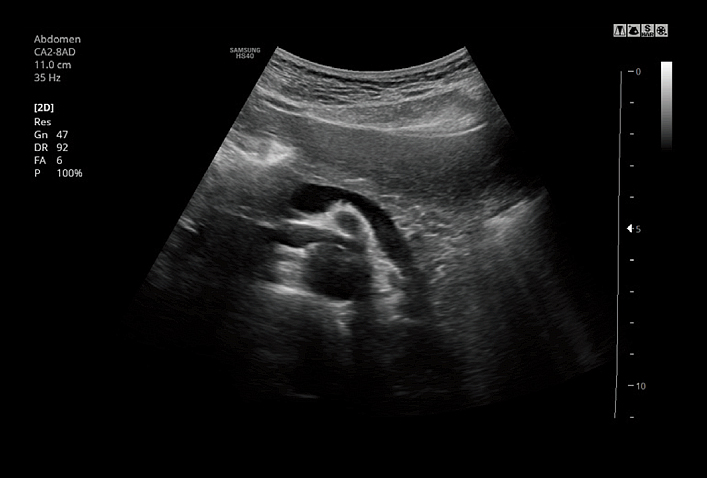

CA2-8ADApplication:Abdomen, Obstetrics, Gynecology, Pediatric, Musculoskeletal, Vascular, Urology, Emergency |

Panoramic imaging displays as an extended field-of-view so users can examine wide areas that do not fit into one image as a single image. Panoramic imaging also supports angular scanning from linear transducer data acquisition.